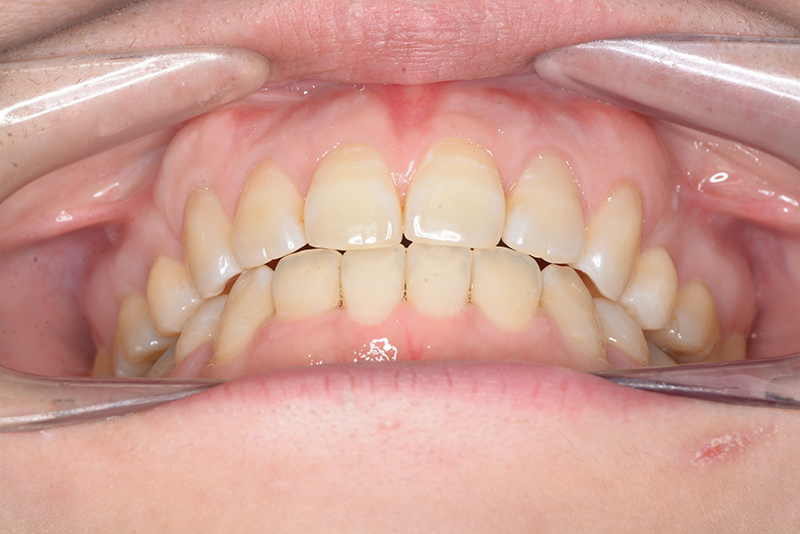

| 主訴 | 前歯で物が噛めない | 診断名 | アングルⅠ級開咬症例 | ||||

|---|---|---|---|---|---|---|---|

| 初診時年齢 | 37歳8ヵ月 | 性別 | 女 | 動的治療期間 | 23ヵ月 | ||

| 批評・予后 | 治療後において下顎角の開大も認められず歯軸の整直、咬合の緊密化が得られた。また上下顎前歯の後退と共に口元の突出感と口唇閉鎖不全の改善が認められた。 |